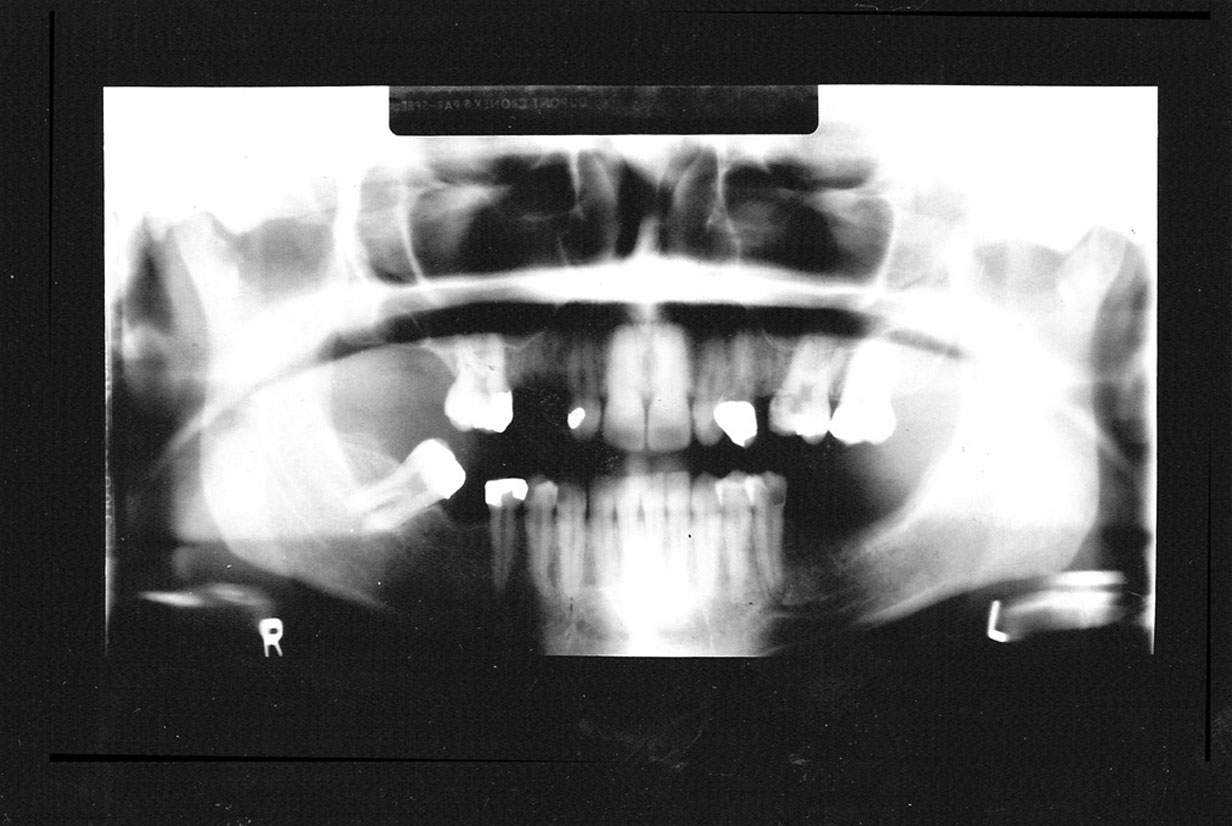

Vertical Height

If the patient’s head is positioned too high, or if the film cassette and tubehead are too low, the superior part of the condyles of the ramus and much of the maxilla will be missing from the film, as in Figure 20. In the reverse situation, if the patient’s head is too low, or the cassette and tubehead are too high, the lower border of the mandible will be lost.

Figure 20. Vertical height.

Figure 20